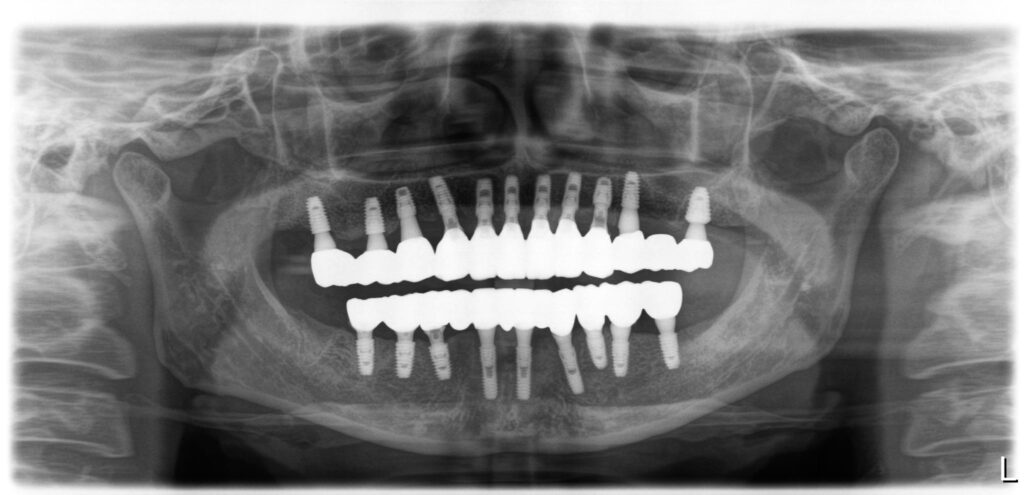

치료후 파노라마 사진입니다. 식립가능한 치아자리에는 임플란트를 식립했고, 브릿지 타입으로 치아와 유사한 모양으로 보철을 완성했습니다. 맞춤지대주에 지르코니아를 이용해서 보철을 했으며, 중요하게 보아야 하는 부분은 치아와 치아사이에 구멍이 있어서 치간치솔 사용이 가능하게 디자인되었다는 점입니다.

간혹, 임플란트보철이 너무 뚱뚱하게 만들어지는 경우 치아와 치아사이에 치간치솔 사용이 불가능한 경우가 있는데 그런 경우에는 위생관리가 어려워 임플란트주위염이 생겨 결국 임플란트를 잃게 될 수도 있습니다.